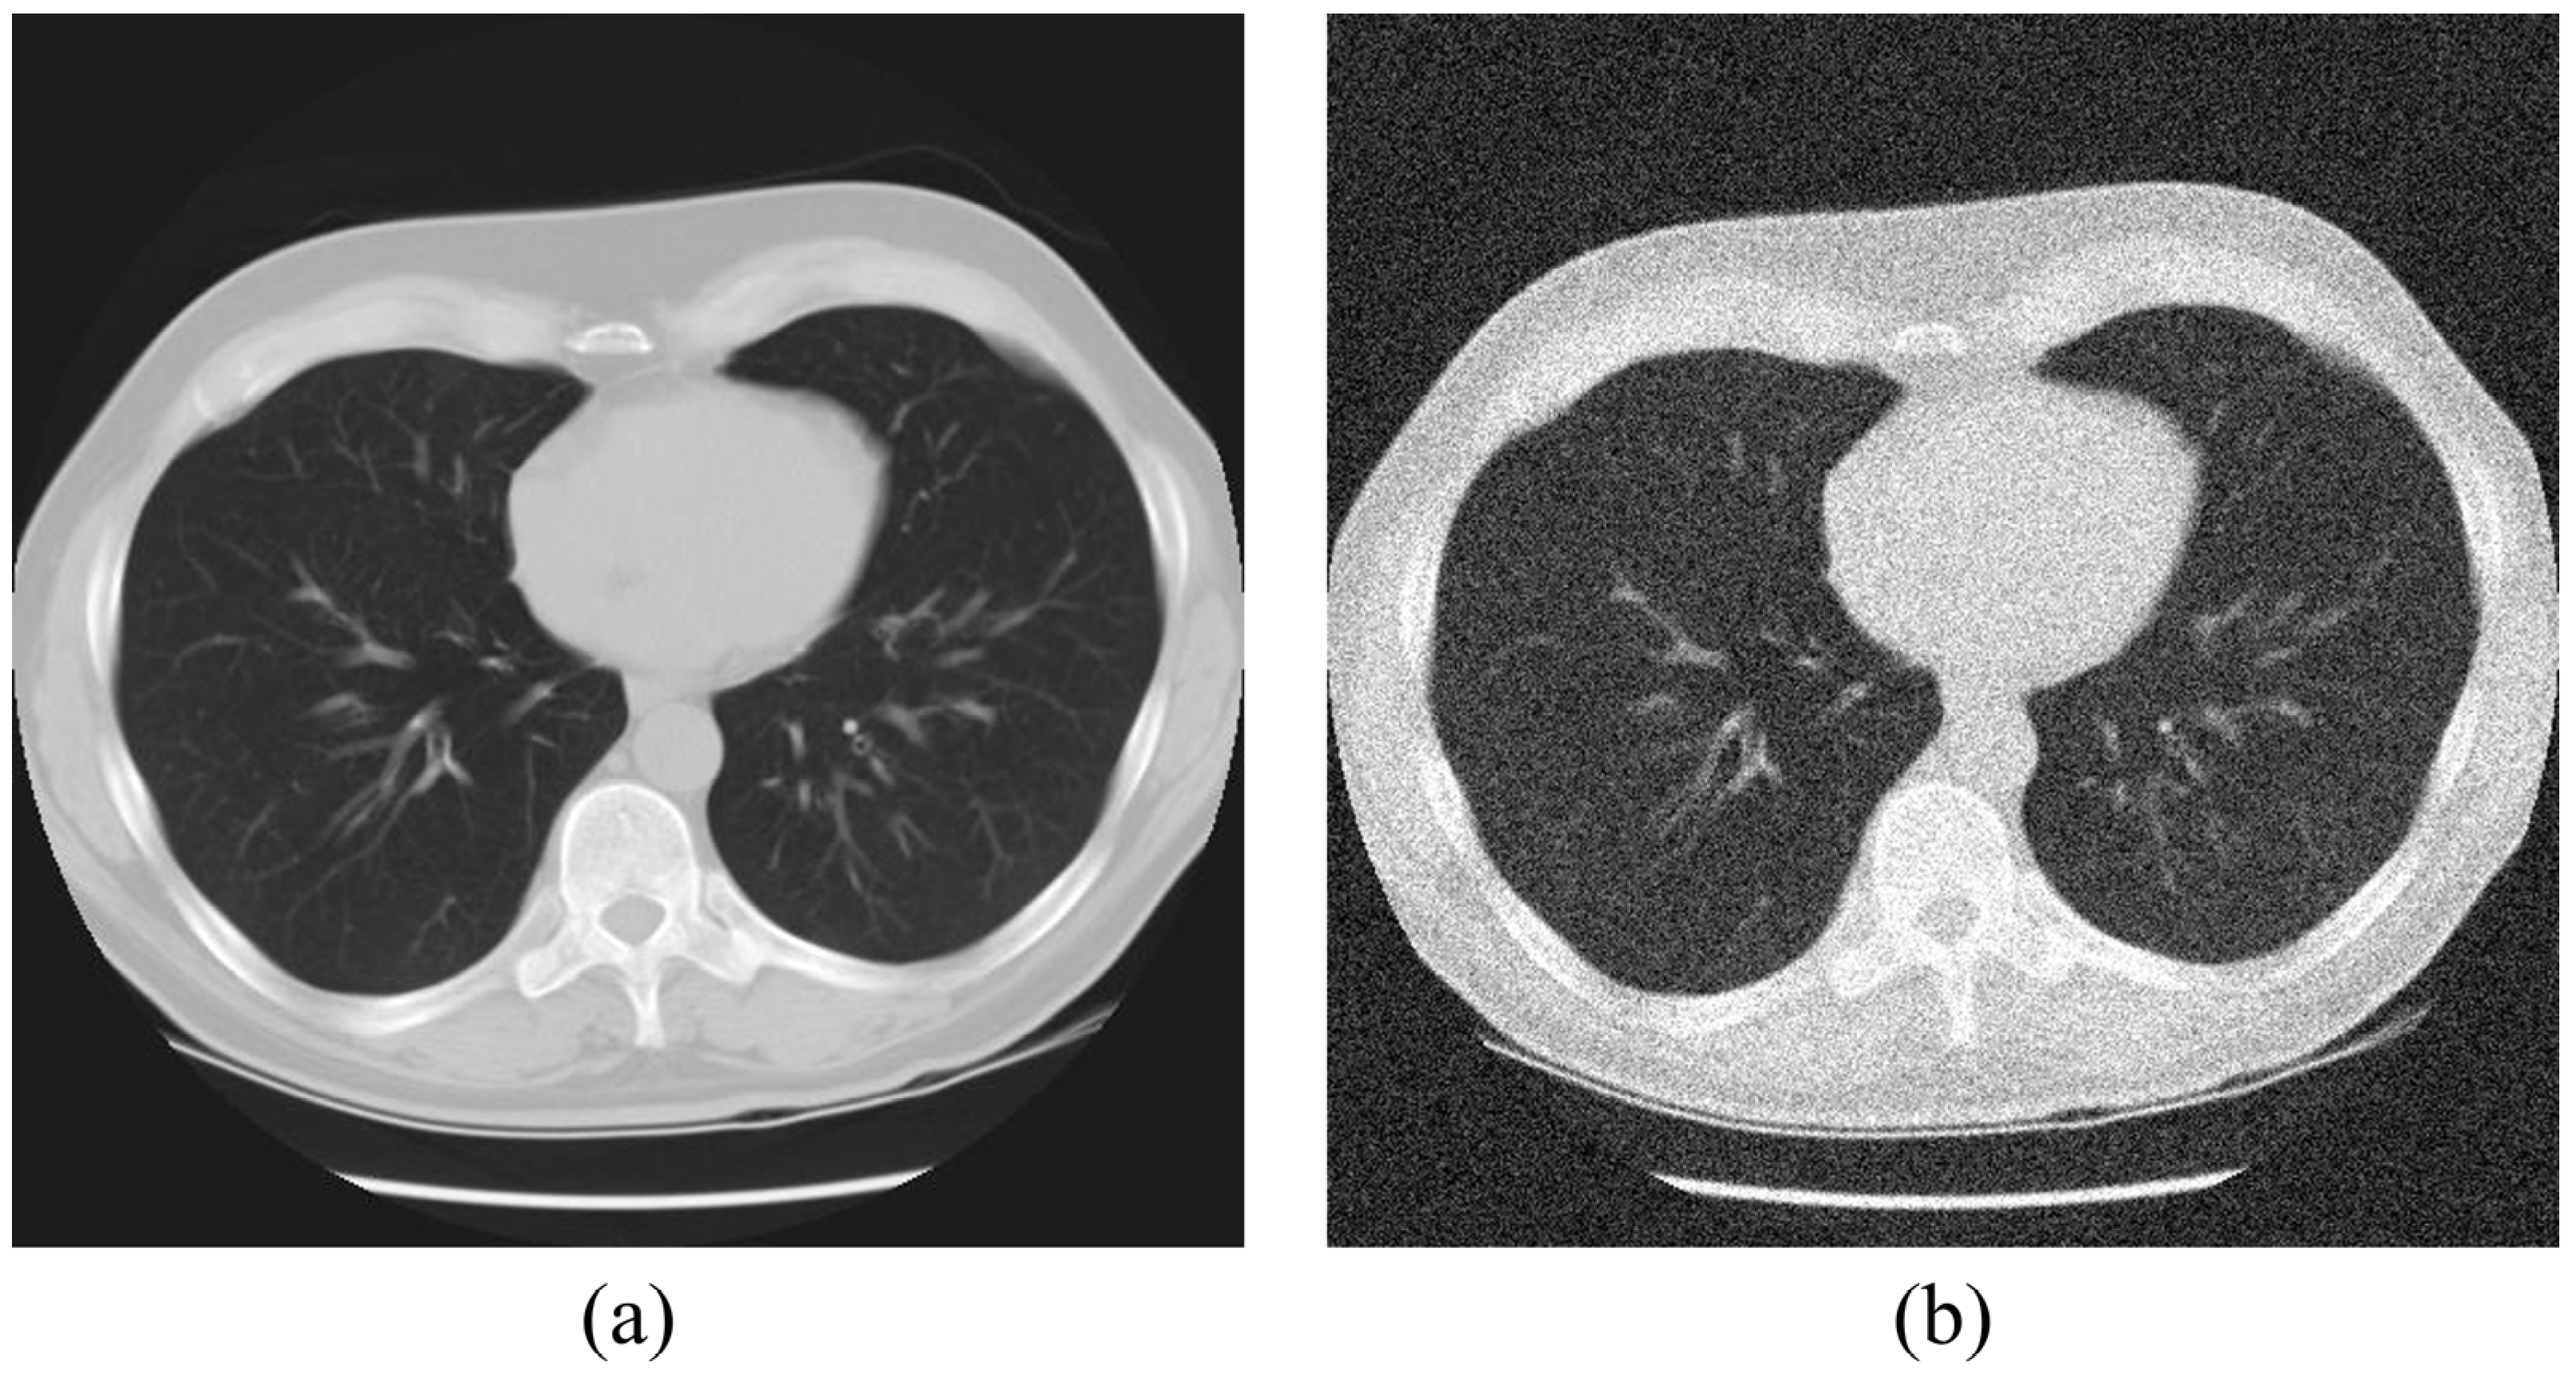

We obtained lung CT images with a tube voltage of 120 kV, tube current of 160 mA, and slice thickness of 2.5 mm using data from the NLST dataset. Subsequently, two images were selected before and after segmenting the slice image, and five slice images were summed and averaged to obtain a standard image. To simulate conditions similar to those of low-dose CT images, Gaussian noise with a mean of 0 and variance of 0.05 was added to the acquired standard image using MATLAB [17,18]. Figure 1 shows the standard images with and without the added Gaussian noise.

Figure 1.

Acquired images for (a) standard image (ground truth) and (b) noisy image.